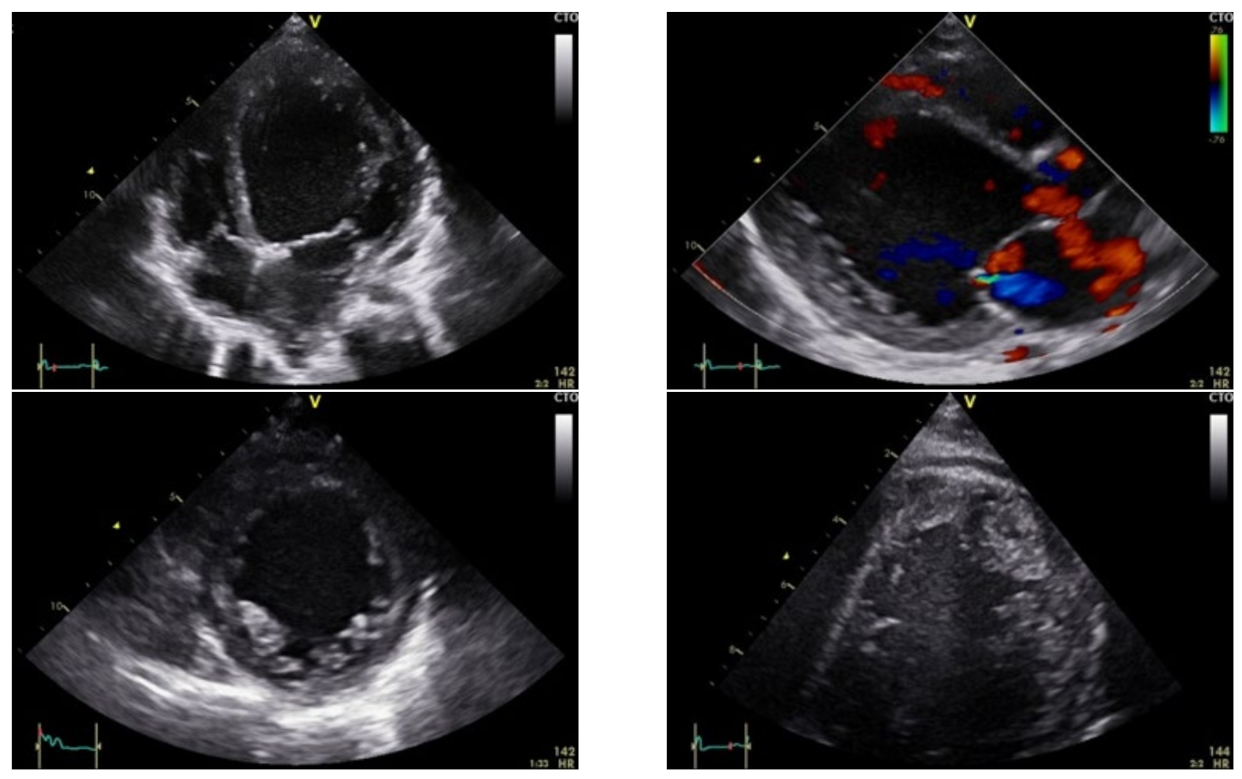

3.1. Case Report 1

3.2. Case Report 2

3.3. Case Report 3